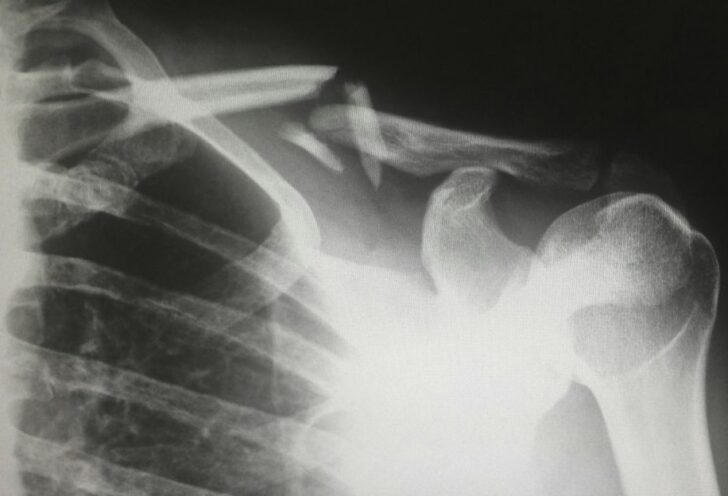

En arbetsskada definieras som en skada som inträffar i samband med arbetet. Detta kan omfatta olyckor som sker på arbetsplatsen, på väg till eller från arbetet, samt arbetssjukdomar som utvecklas över tid på grund av arbetsförhållandena. Arbetsskador innefattar både fysiska skador, exempelvis efter en olycka, och mer långvariga tillstånd som orsakas av arbetsmiljön, som hörselnedsättning eller stressrelaterade sjukdomar.